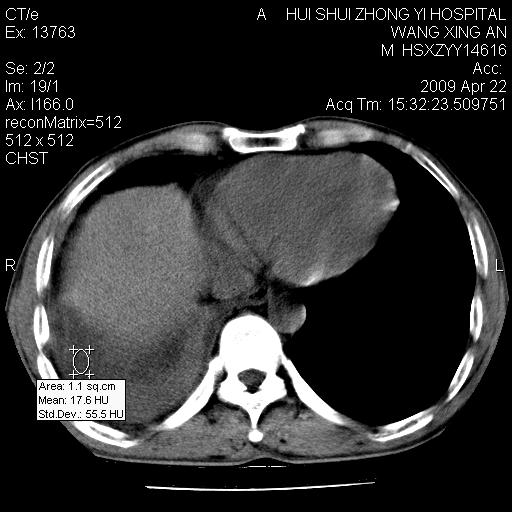

标题: CT19534:患者男、46岁咳嗽、胸痛半月。 [打印本页]

标题: CT19534:患者男、46岁咳嗽、胸痛半月。

中央型肺癌,右侧腹水

1、右下肺中央型肺癌并右肺转移,右肺下叶不张。(肿块围绕右肺下叶支气管生长,致管腔闭塞右肺下叶不张;右肺有结节影)。

2、右侧胸腔积液。

1、右下肺中央型肺癌并右肺转移,右肺中下叶不张。(右肺有结节影)。胸骨转移

1。右下肺中央型肺癌并肺转移,右肺下叶不张。(两肺都有结节影)。

1)右肺中间段支气管癌并右肺下叶肺不张。2)右肺上叶、两肺下叶背段感染性病变。3)右侧少量胸腔积液。